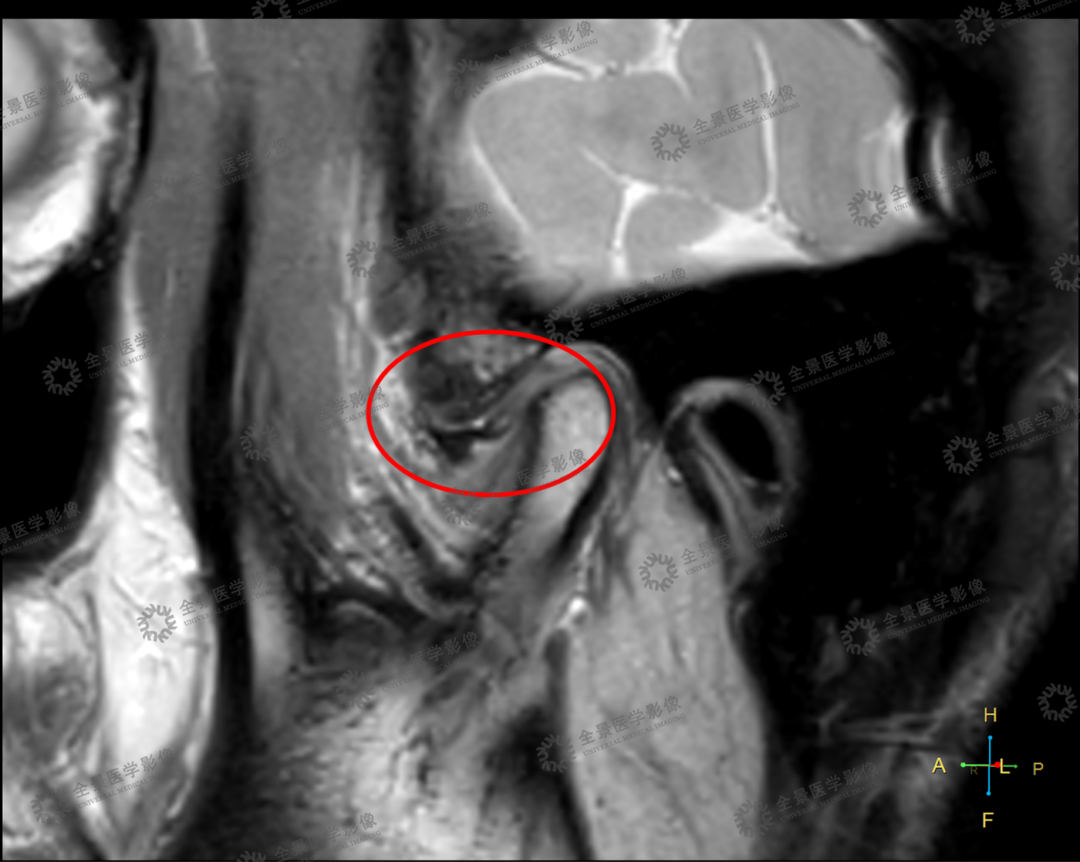

颞下颌关节核磁片子你会看吗

颞下颌关节紊乱为什么要拍核磁共振? - 知乎

颞下颌关节紊乱为什么要拍核磁共振? - 知乎